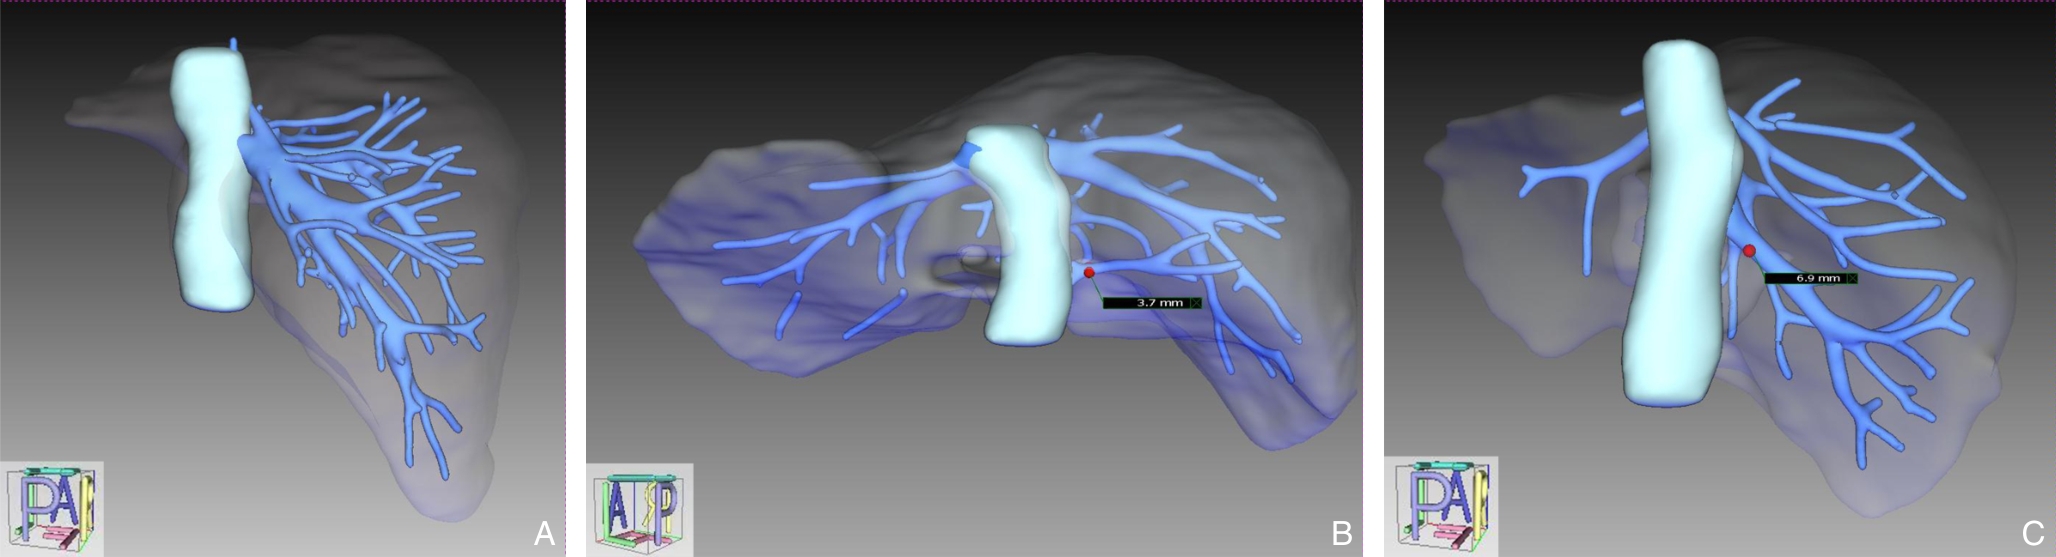

• Application of augmented reality navigation combined with indocyanine green fluorescence imaging in laparoscopic resection of central hepatic tumors

2026, 35(1):88-96. DOI: 10.7659/j.issn.1005-6947.250468

Abstract (100) HTML (82) PDF 2.06 M (167) Comment (0) Favorites

Abstract:Background and Aims Laparoscopic resection of centrally located hepatic tumors remains technically demanding due to the complex anatomical relationships with major vascular structures. Conventional intraoperative ultrasound or indocyanine green fluorescence imaging (ICG-FI) alone has limitations, particularly in visualizing deep anatomical structures. This study aimed to evaluate the clinical value of augmented reality (AR) navigation combined with ICG-FI in laparoscopic resection of central hepatic tumors.Methods A retrospective analysis was conducted on 38 consecutive patients who underwent laparoscopic resection of central hepatic tumors guided by AR navigation combined with ICG-FI between May 2022 and March 2025. Intraoperative navigation performance, surgical parameters, and perioperative outcomes were assessed.Results All 38 procedures were completed laparoscopically without conversion. The intraoperative tumor fluorescence detection rate was 100%. The mean operative time was (324.9 ± 132.4) min, and the median intraoperative blood loss was 400 (50-1 200) mL. The mean registration error was (6.3±0.6) mm. The median number of predicted and verified vessels was 6 (4-8) and 7 (5-10), respectively. R0 resection was achieved in all patients, with a mean surgical margin of (1.5±0.5) cm. The postoperative complication rate was 13.2%, with no severe complications such as intra-abdominal hemorrhage, gas embolism, or liver failure. The median postoperative hospital stay was 9 (4-20) days. During a median follow-up of 20 months, no tumor recurrence was observed.Conclusion The combined use of AR navigation and ICG-FI enables intraoperative prediction and verification of critical vascular structures and facilitates precise control of the transection plane in laparoscopic resection of central hepatic tumors. This technique improves surgical precision and safety and shows promising clinical potential.